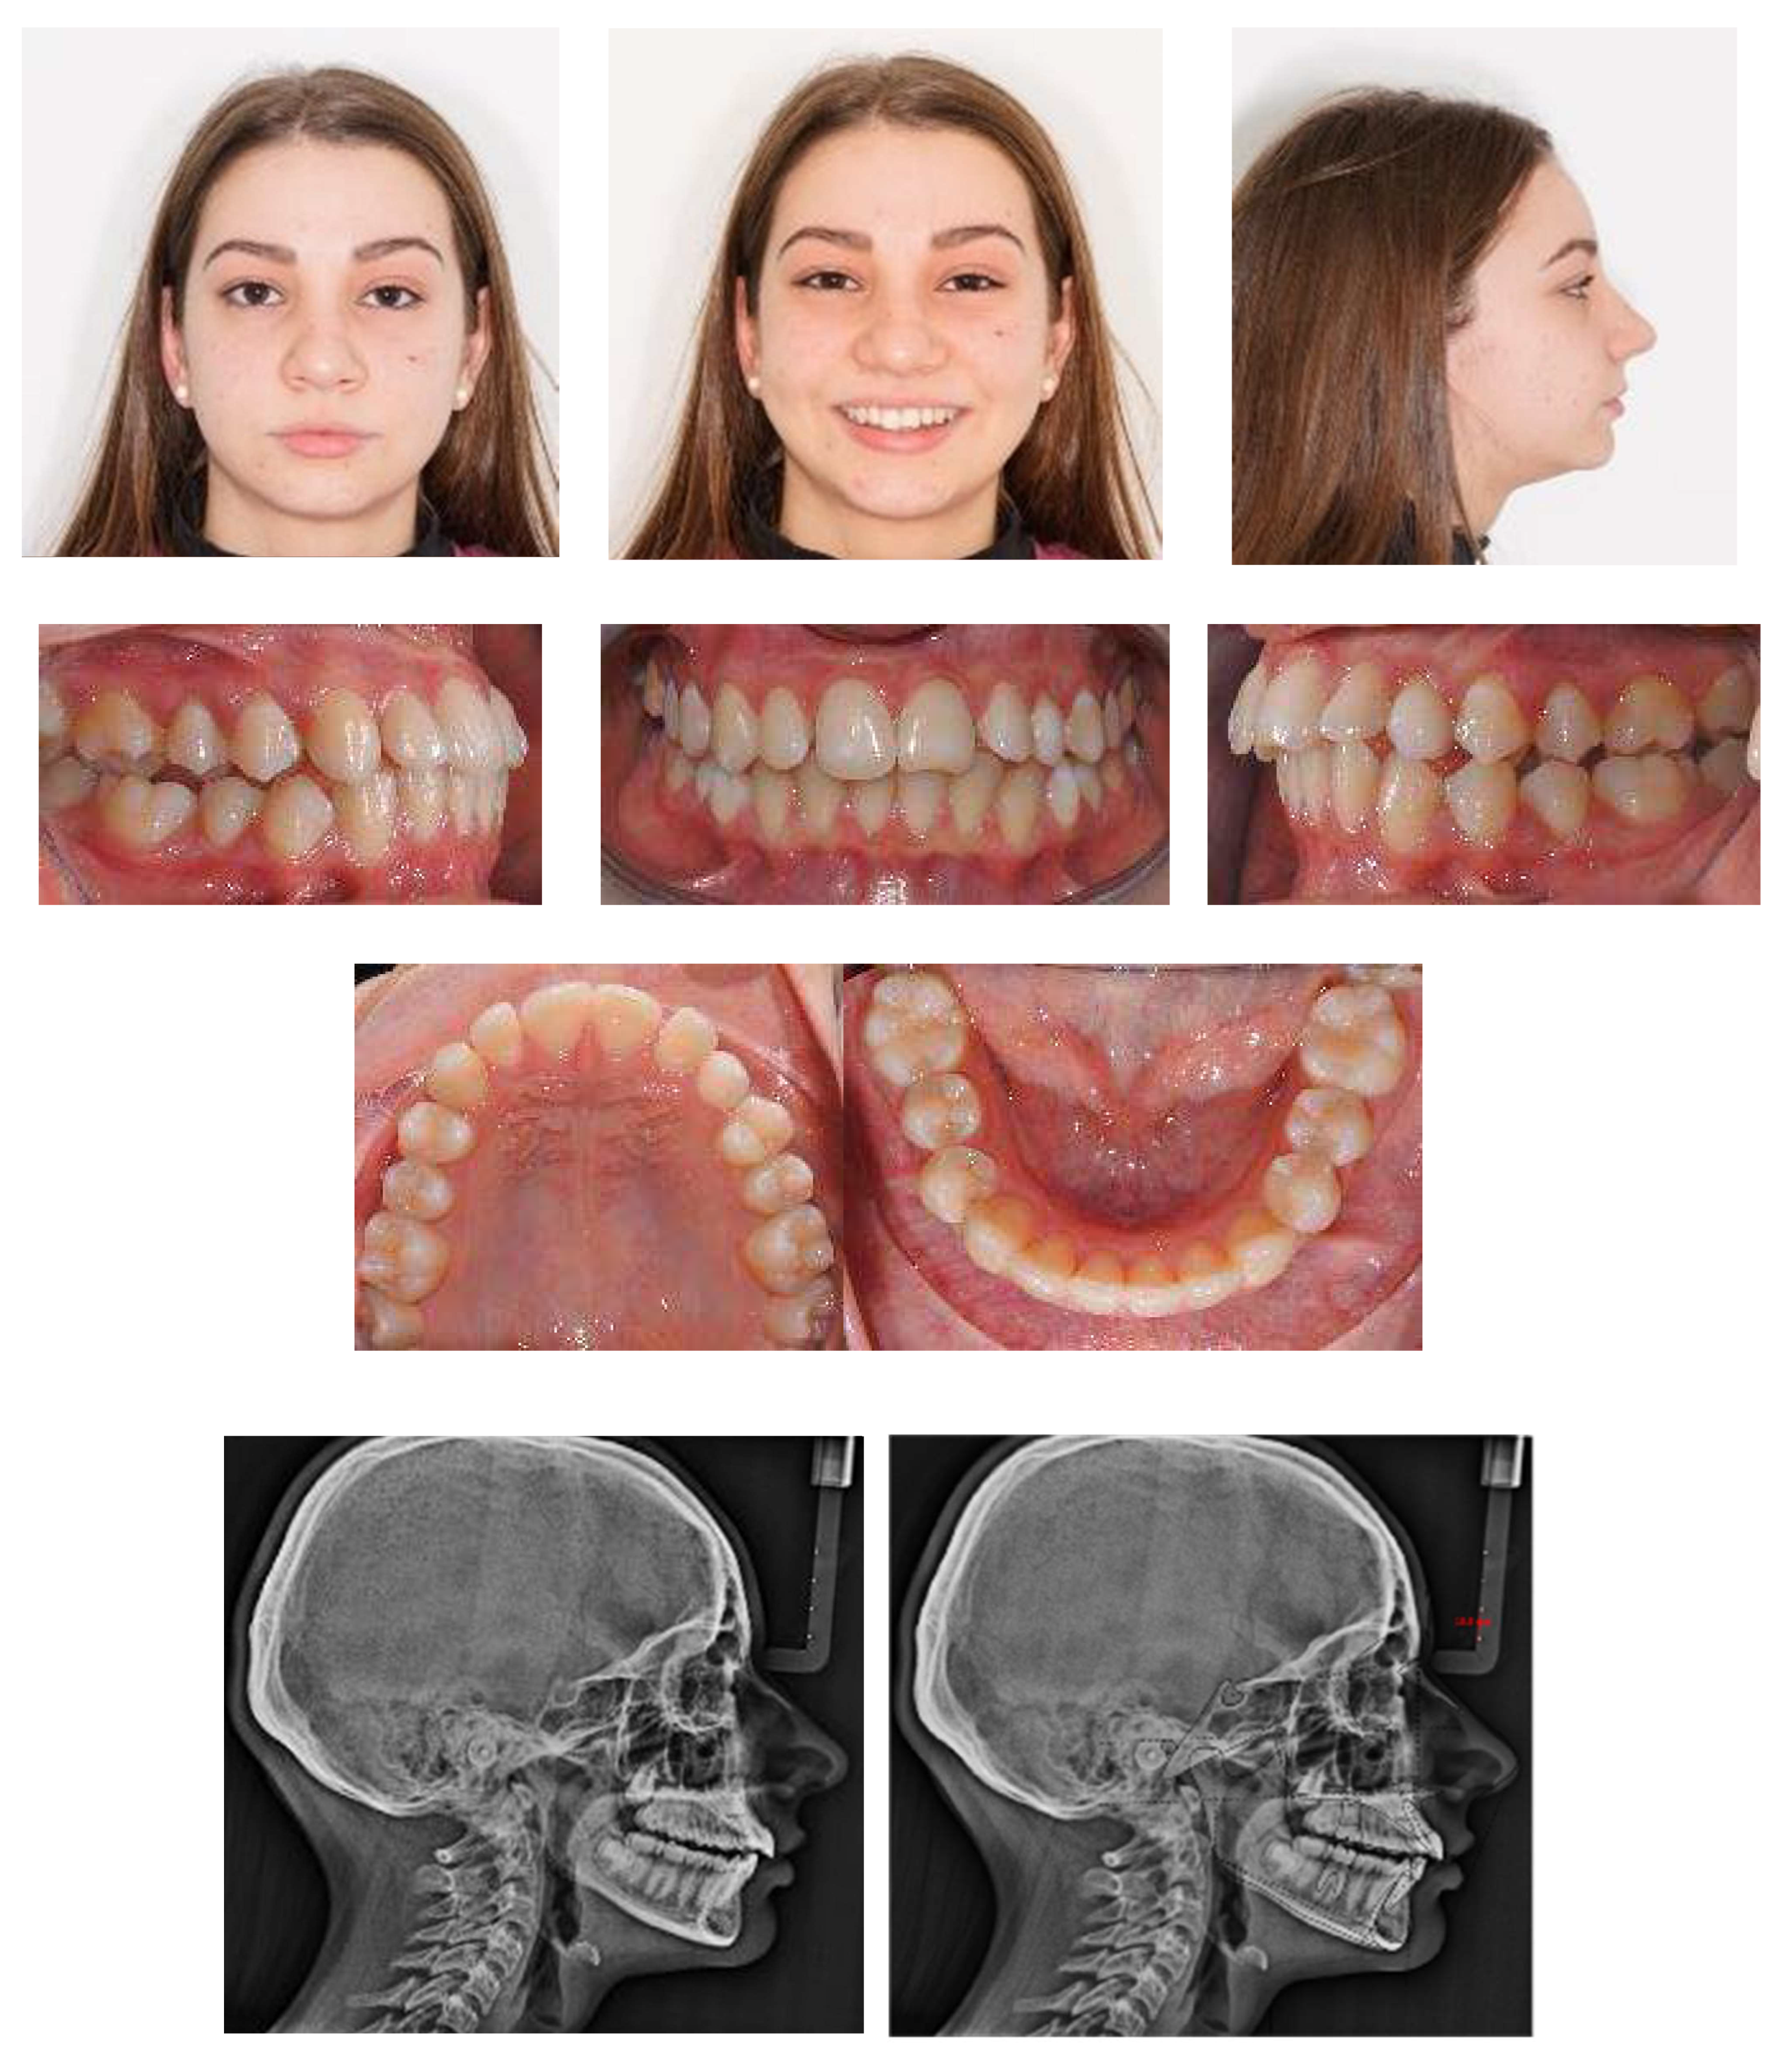

An 18-year-old female patient was referred, complaining of unpleasant smile. She presented good general health and no systemic or congenital diseases. From a frontal view, the patient presented a well-proportioned three-thirds of her face and no evidence of asymmetry. From the lateral view, the profile appeared convex with well-represented nasolabial angle, labiomental sulcus, and lip competence. Intraorally, the patient showed a Class II malocclusion with the molar Class I relationship, edge to edge canine relationship on both sides, increased overjet, overbite, and the retention of the 63. Panoramic, lateral headfilm, and dental cast records were taken (Figure 11).

An 18-year-old female with dentoskeletal Class II with impacted upper left canine before treatment.

The initial cephalometric analysis showed a skeletal Class I relationship (ANB, +2.6°) and mesodivergent pattern with the proclination of the upper (I/ANS-PNS 118.8°) and lower (i/GoGn:102.2°) incisors. All the radiographic findings, the age of the patient, the prolonged deciduous retention, and the risk of root resorption of the adjacent tooth, led clinicians to conclude that the permanent canine would not erupt properly without intervention (Table 2).

The position of the impacted canine showed an alpha angle of 58° and the Ericson and Kurol II sector classification. No clinical symptoms on articular examination were detected (Figure 12).

Pre-treatment panoramic X-ray with the evaluation of alpha angle and sector according to the Ericson and Kurol classification.